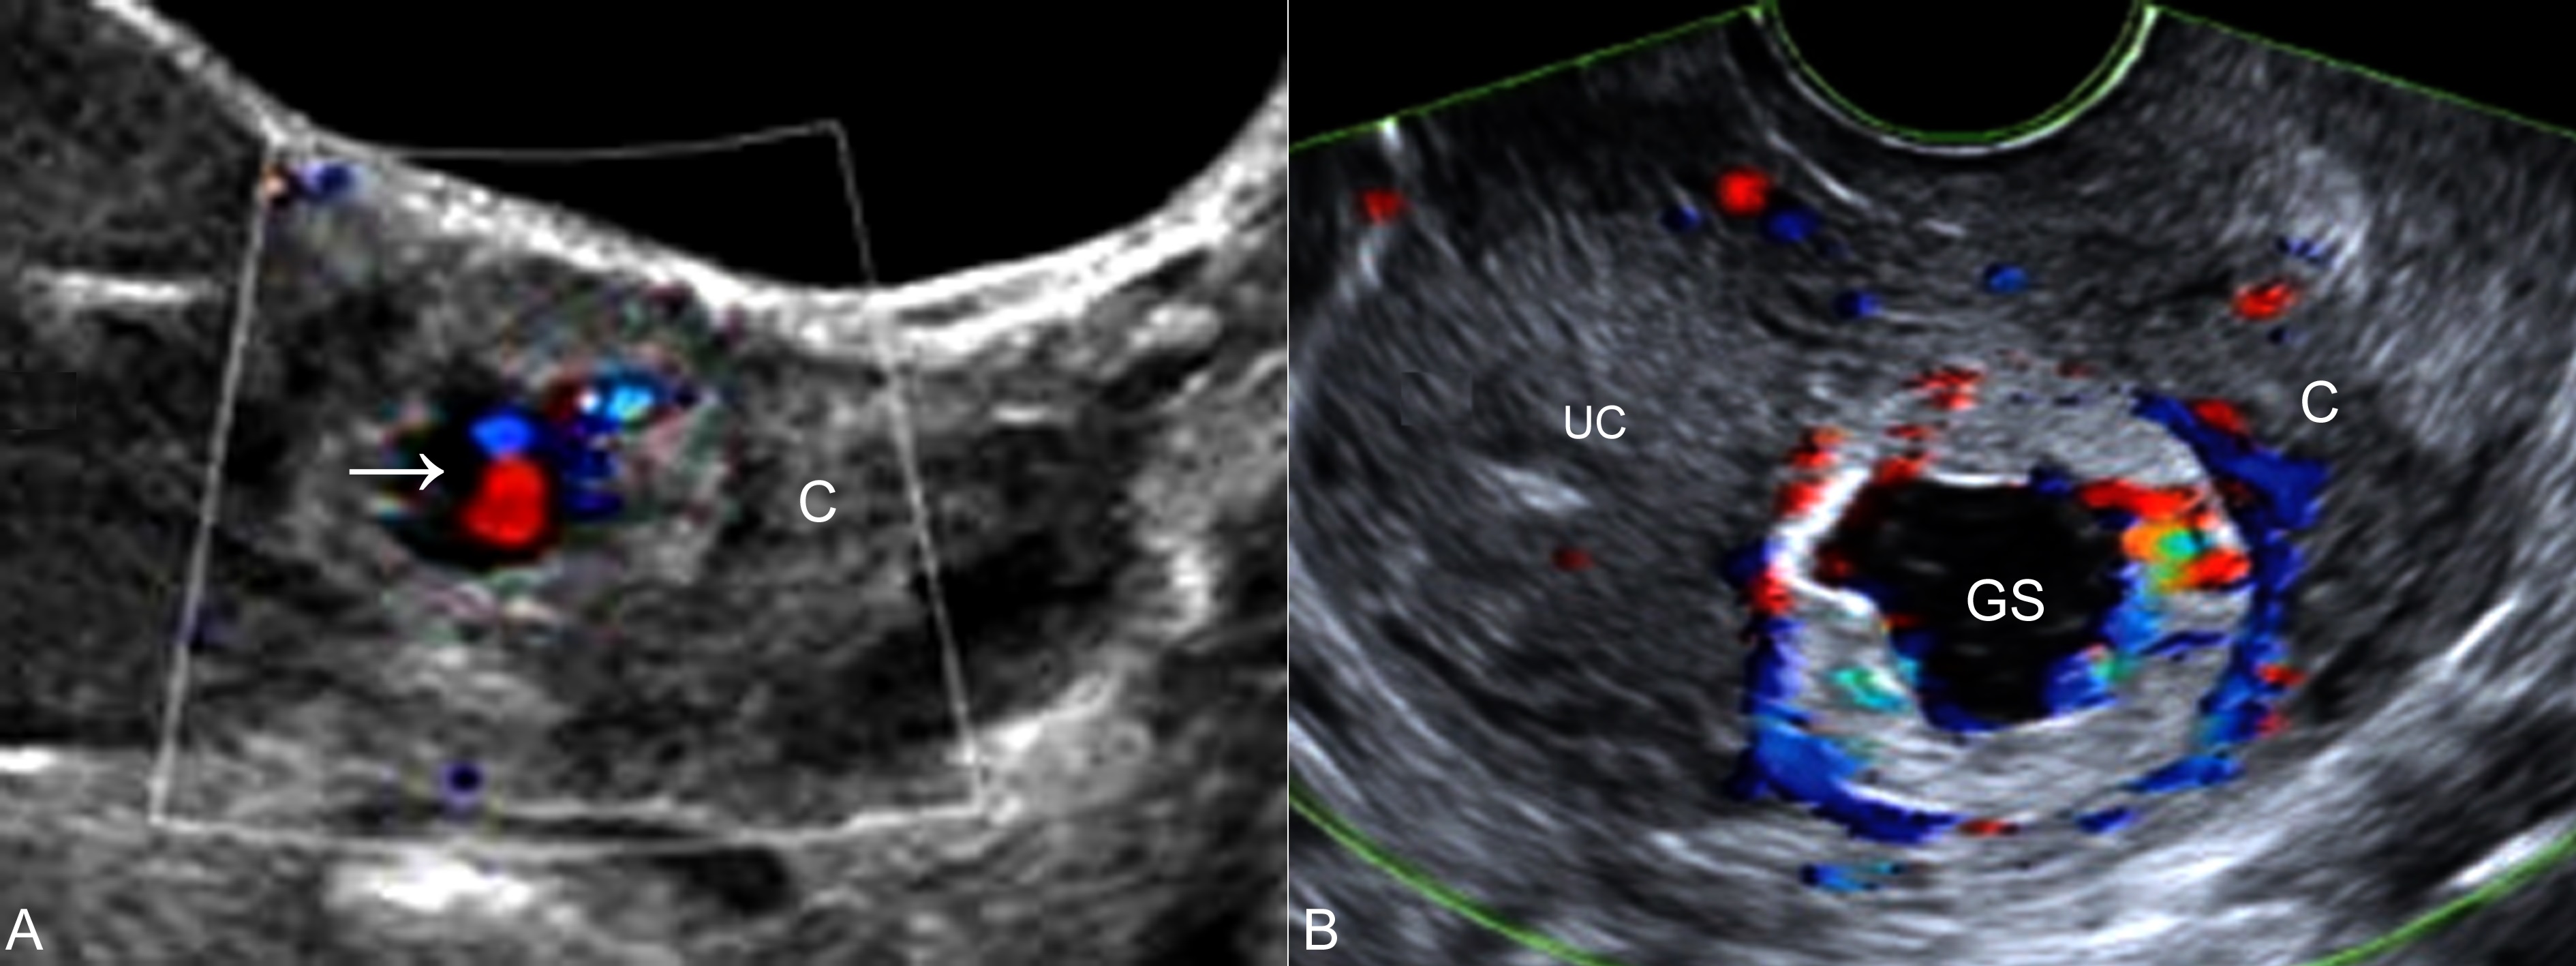

图1肌壁间妊娠声像图

A:TAU,子宫颈部(C)显示孕囊回声,CDFI检查内部可见胚胎血流(箭头)

B:TVU,宫腔(UC)处未见妊娠征象,宫颈部(C)孕囊(GS)周围显示血流增多

超声显像检查显示子宫肌层内孕囊回声,早期孕囊较小时呈现偏心状,距子宫浆膜面的距离<5mm,孕囊与子宫腔无关系;CDFI检查同正常妊娠,局部血流显示增多(图1),子宫动脉显示血流增多,阻力降低。三维超声检查可以更好地对孕囊进行定位显示,观察孕囊与子宫腔的关系。